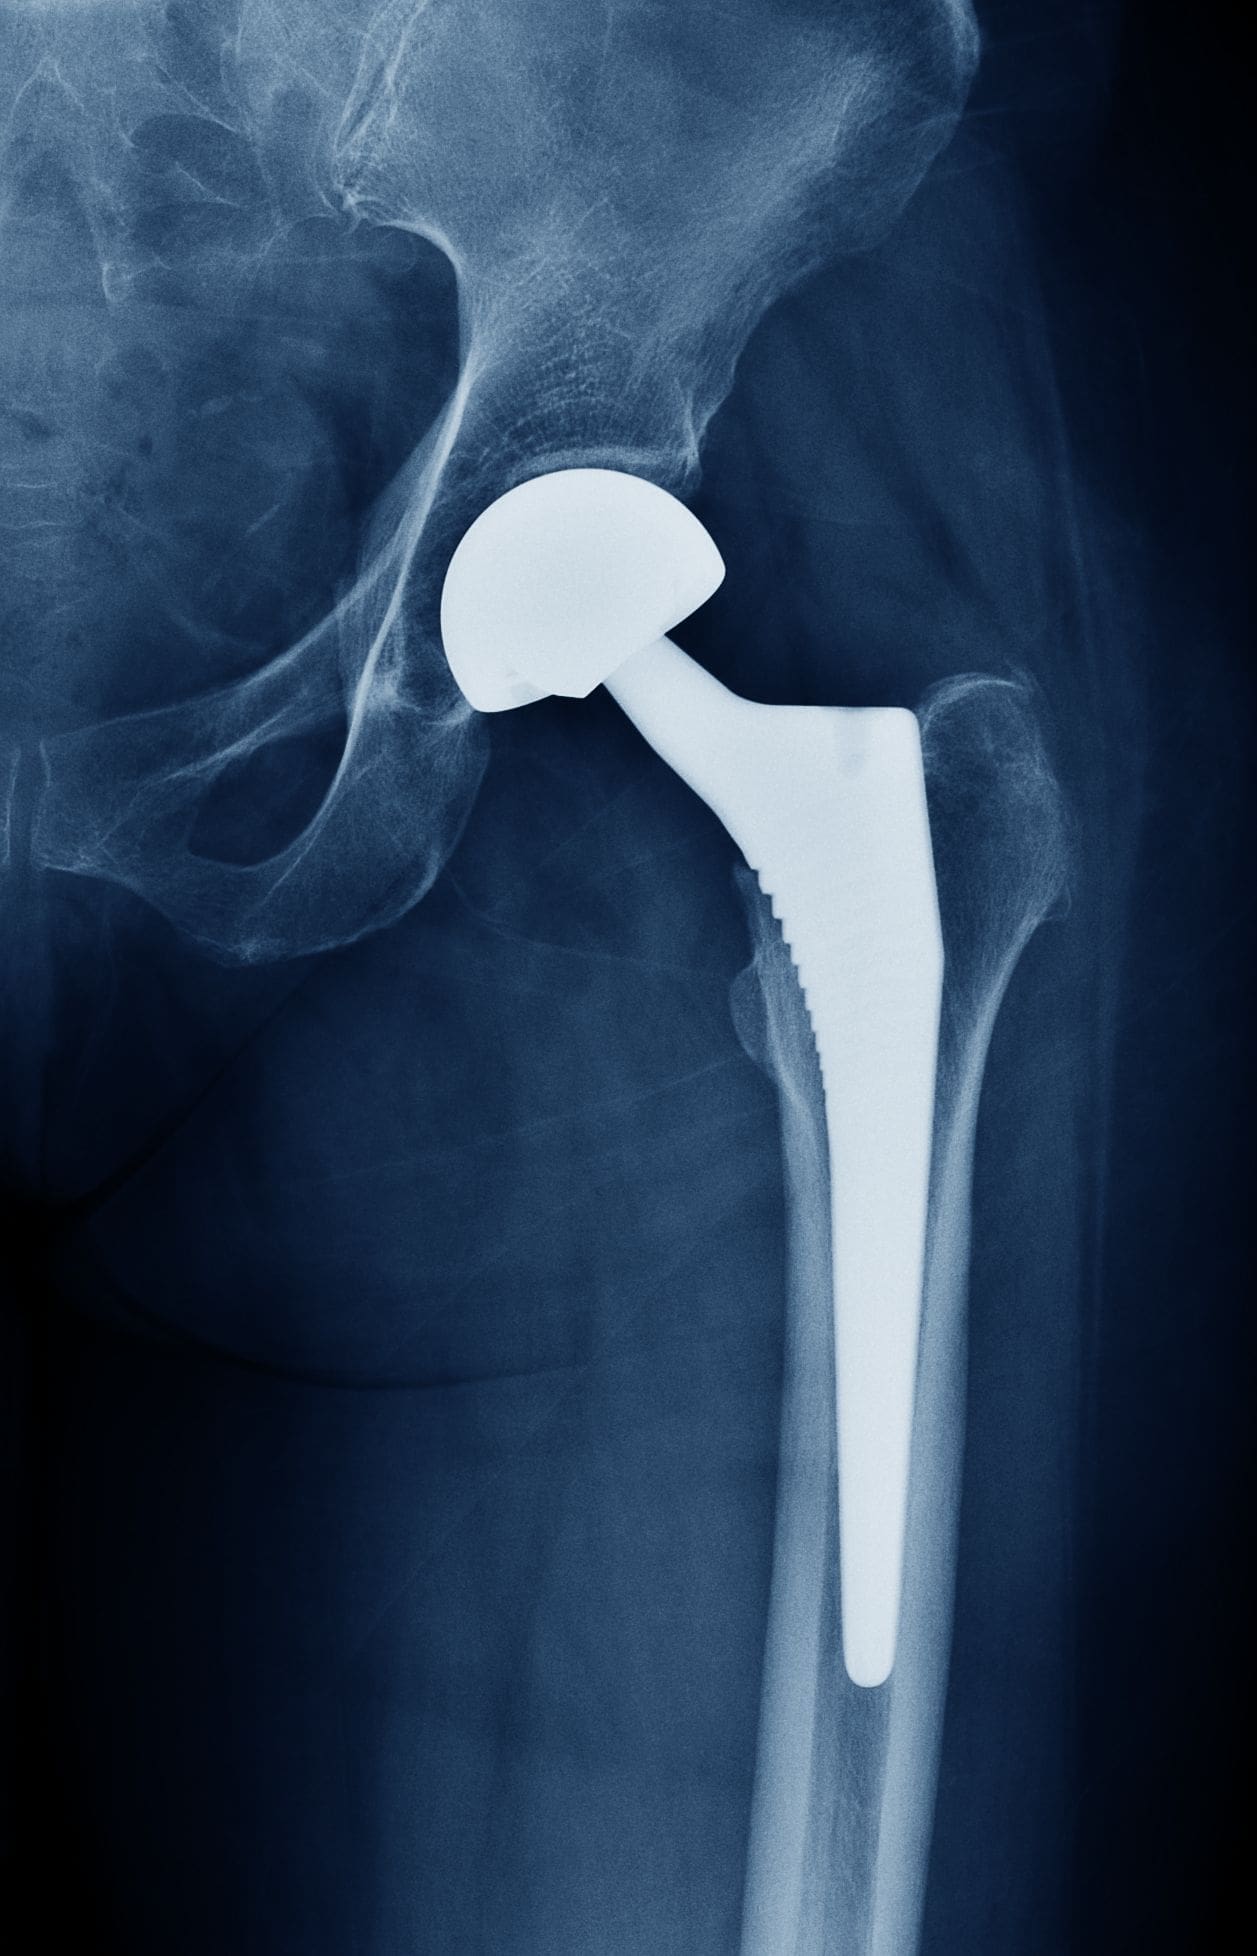

Eine Hüftprothese ersetzt die verschlissenen Teile des natürlichen Hüftgelenks. Sie besteht in der Regel aus drei Hauptkomponenten:

Pfannenkomponente (Acetabulumkomponente): Diese Komponente ersetzt die natürliche Hüftpfanne. Sie besteht meist aus einer Metallschale, die in das Beckenknochen eingesetzt wird. Innerhalb dieser Schale befindet sich ein Einsatz (Inlay), der die eigentliche Gelenkfläche bildet. Dieser Einsatz kann aus verschiedenen Materialien bestehen, z.B. hochvernetztem Polyethylen (Kunststoff), Keramik oder Metall.

Hüftkopf (Femurkopf): Der künstliche Hüftkopf ersetzt den natürlichen Hüftkopf am oberen Ende des Oberschenkelknochens. Er besteht meist aus einer Metallkugel oder Keramik. Die Größe des Hüftkopfes wird individuell an die Anatomie des Patienten angepasst.

Schaft (Femurschaft): Der Schaft wird in den Oberschenkelknochen eingebracht und verankert den künstlichen Hüftkopf. Er besteht in der Regel aus einer Metalllegierung, z.B. Titan oder Kobalt-Chrom-Molybdän. Die Verankerung kann zementfrei oder mit Zement erfolgen. Das ist ein spezieller Knochenzement zur Befestigung.